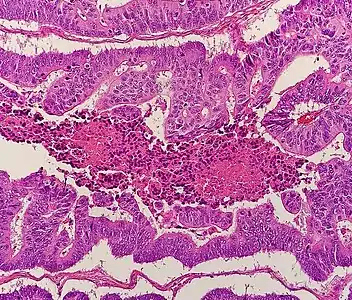

Histopathology

Relative incidence of various histopathological types of colorectal cancer. The vast majority of colorectal cancers are adenocarcinomas.[74]

Micrograph of colorectal adenocarcinoma, showing "dirty necrosis".

The histopathologic characteristics of the tumor are reported from the analysis of tissue taken from a biopsy or surgery. A pathology report contains a description of the microscopical characteristics of the tumor tissue, including both tumor cells and how the tumor invades into healthy tissues and finally if the tumor appears to be completely removed. The most common form of colon cancer is adenocarcinoma, constituting between 95%[75] to 98%[76] of all cases of colorectal cancer. Other, rarer types include lymphoma, adenosquamous and squamous cell carcinoma. Some subtypes have been found to be more aggressive.[77] Immunohistochemistry may be used in uncertain cases.